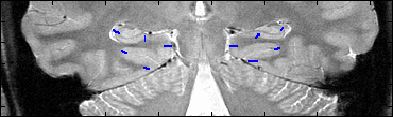

This is an example of one subjects demarcation. The A/P slice is slice

3.

5